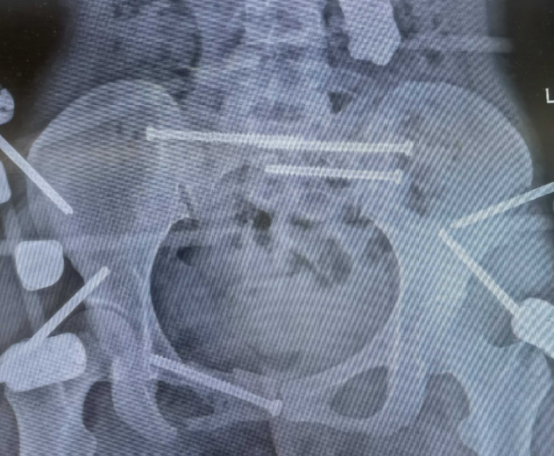

6月19日中午,在刘华水主任的指导下,孙延斌副主任、李上主治医师为患者实施“骨盆骨折闭合复位内固定术”,大致分为两步:一是以固定针、固定架使双侧骶髂关节复位;二是处理耻骨骨折。孙延斌副主任医师介绍说:“这次手术的时间很短,只有29分钟,属于速战速决,为什么?因为需要保住性命,需要稳定各项生命体征。”

7月2日,在刘华水主任的指导下,孙延斌副主任、李上主治医师再次为患者实施手术。李上博士介绍说:“这一次所实施的骨盆骨折切开复位螺钉内固定术,主要解决耻骨相关问题,包括清理骨折断端,使用精准微创技术复位螺钉固定,以及双侧骶髂螺钉固定,另外还进行了右下肢损伤部位切开清创。这一切处置措施,都是在生命体征平稳的基础上进行的,本次手术有助于患者进行肢体功能康复训练。”

*2025年7月2日第2次手术后